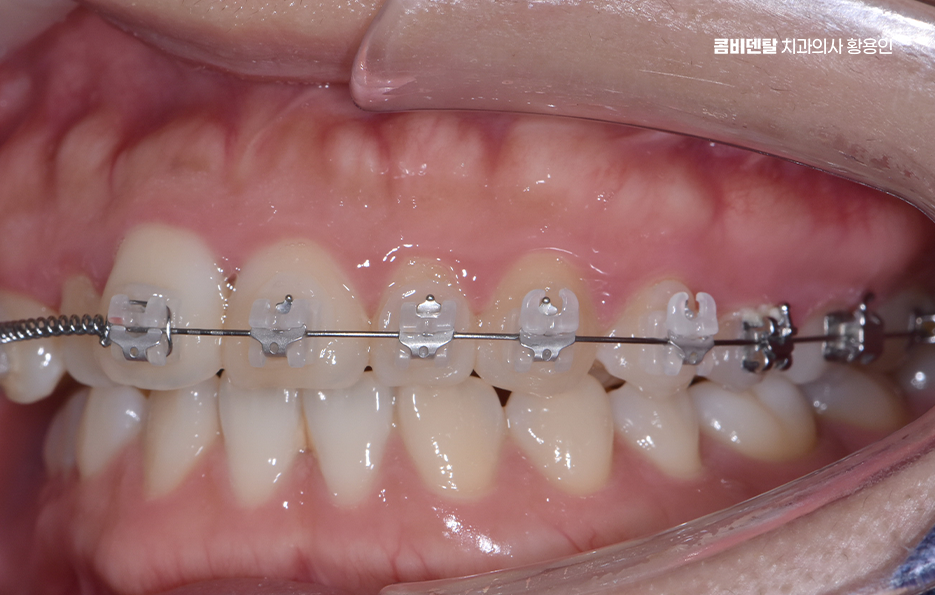

교정 장치의 종류에 따라서도 통증의 정도가 다를 수 있는데 일반적인 금속 브라켓을 사용하는 경우, 초기에는 금속이 입 안쪽에 닿으면서 불편함을 느낄 수 있어요. 특히 교정 와이어를 조절할 때마다 일정한 힘이 가해지기 때문에 몇 일 동안은 씹는 것이 불편할 수도 있지만 반면, 클리피씨 같은 자가 결찰형 브라켓을 사용하는 경우, 마찰력이 줄어들면서 치아 이동 속도가 상대적으로 빠르고, 통증이 덜하다고 느낄 수 있어요. 또한 투명 교정이나 인비절라인 같은 경우에는 탈착이 가능하고 교정기로 인한 통증이 일반교정에 비해 상대적으로 덜한 편이라는 특징이 있어요